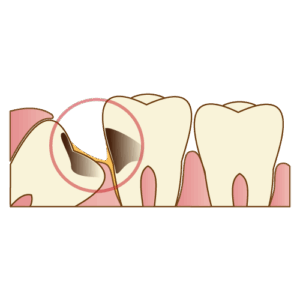

あごのスペースが足りないと、ちょっと窮屈に生えてきてしまい、

横向きになったり、半分だけ顔を出したりと、個性的な生え方をするのが特徴です。

むし歯

磨きにくい場所にあるので、親知らずだけでなく、

なんと 手前の歯までむし歯にしてしまう ことがあります。

歯並びへの影響

横向きに生えていると、前の歯へ押す力がかかってしまい、

歯並びが乱れちゃう場合も…!

抜いたほうが良いケース

横向き・斜め向きで汚れがたまりやすい

手前の歯をむし歯にしてしまっている